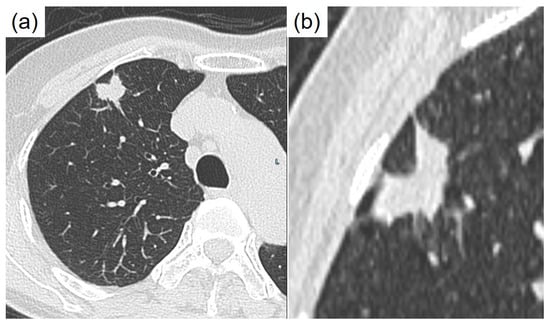

Tachibana, M.; Ito, Y.; Fujikawa, R.; Tsukamoto, K.; Uehara, M.; Kobayashi, J.; Hayashi, T. Lung Adenocarcinoma Exhibiting Thanatosomes (Hyaline Globules), Cytoplasmic Clearing, and Nuclear Pleomorphism, with a KRAS Mutation. Diagnostics 2025, 15, 894. https://doi.org/10.3390/diagnostics15070894